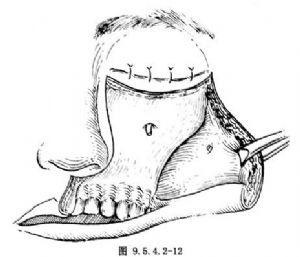

(2)自骨膜下分離頰部軟組織瓣並翻向外側,切斷眶下神經,顯露眶下緣,上頜竇前壁,梨狀孔,上牙槽骨上部及顴骨(圖9.5.4.2-12)。